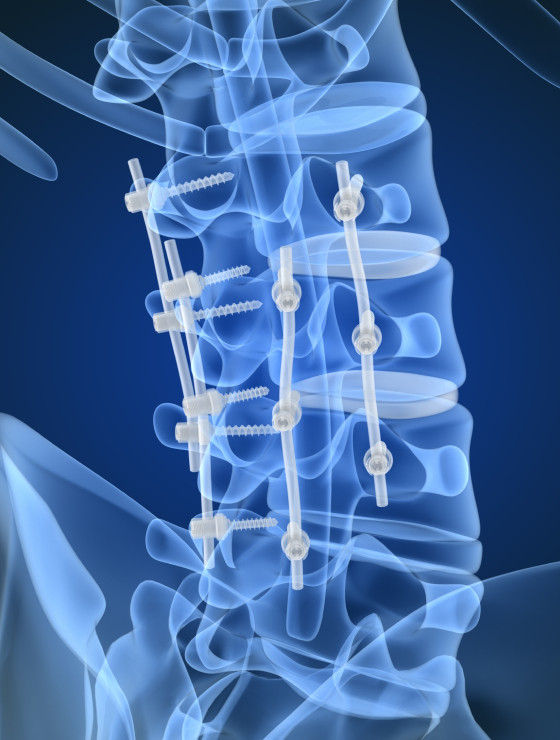

Cirurgias na coluna são seguras e previsíveis. Ao longo das últimas décadas observou-se refinamento das técnicas operatórias e dos equipamentos de projeção de imagens, como microscópios e vídeo-endoscópios. Hoje é possível “navegar” em cirurgias guiadas por tomografia tridimensional, além de monitorar a atividade neurológica do paciente em tempo real.

Dr. Fernando Soccol é médico ortopedista referência em cirurgia da coluna vertebral, com mais de uma década de experiência, expoente na área de cirurgia minimamente invasiva e cirurgia endoscópica da coluna.